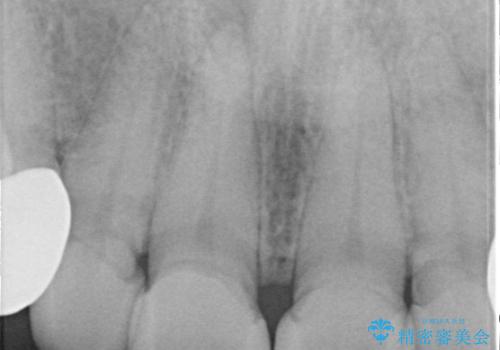

- 他院で1年ほど前にセラミッククラウンを入れたそうですが、しばらくしてから歯茎から膿が出てきたそうです。

歯髄診にて歯髄が失活していることが判明したため、クラウンを除去し根管治療を行ってから、再度オールセラミッククラウンを作成しています。

今回のケースはクラウン除去した際に露髄点は認められなかったため、形成時の発熱が原因であったと推測しています。